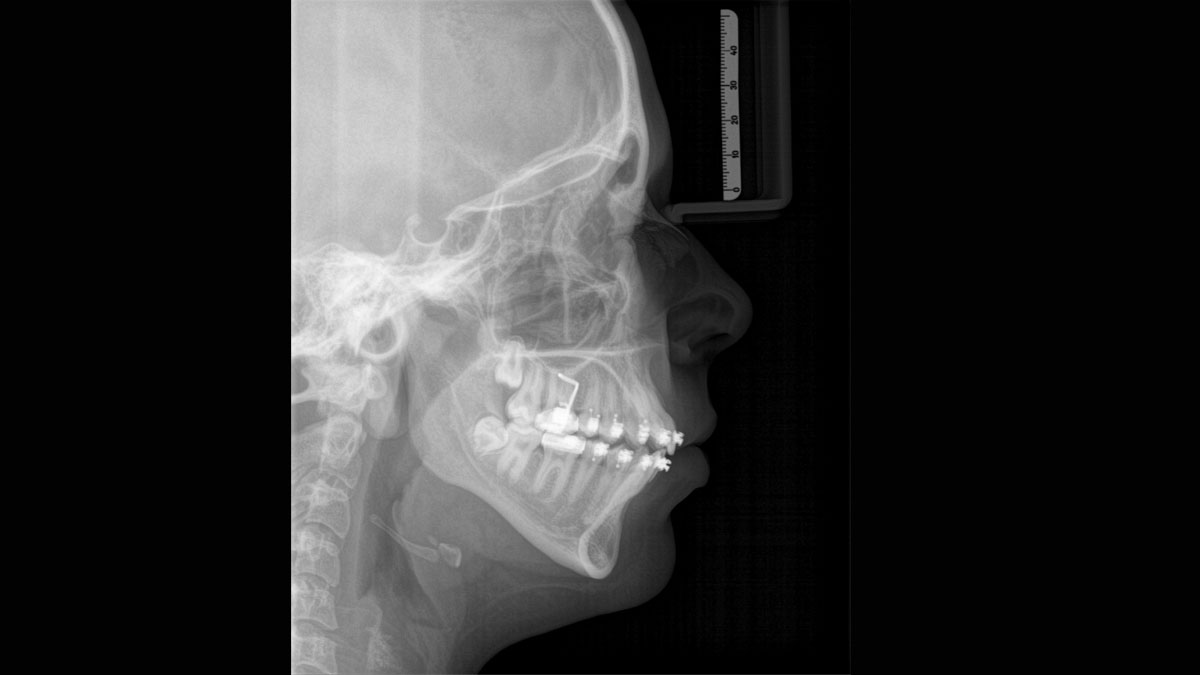

For exceptional panoramic images with high sharpness. You can choose an optional right or left cephalometric arm, which can be retrofitted at any time

Axeos – the 2D/3D specialist system with a large volume and high image quality for practices with a broad treatment offering. Developed together with dentists and clinicians, Axeos provides the fullest range of functions out of all Dentsply Sirona extraoral X-ray devices. In addition to excellent image quality and tailor-made 3D volume sizes, the dental imaging device is fully optimized for enhanced patient comfort. Axeos not only provides quality in performance and comfort, but also with its award-winning design thanks to the integrated bite block accessory cabinet and ambient light.